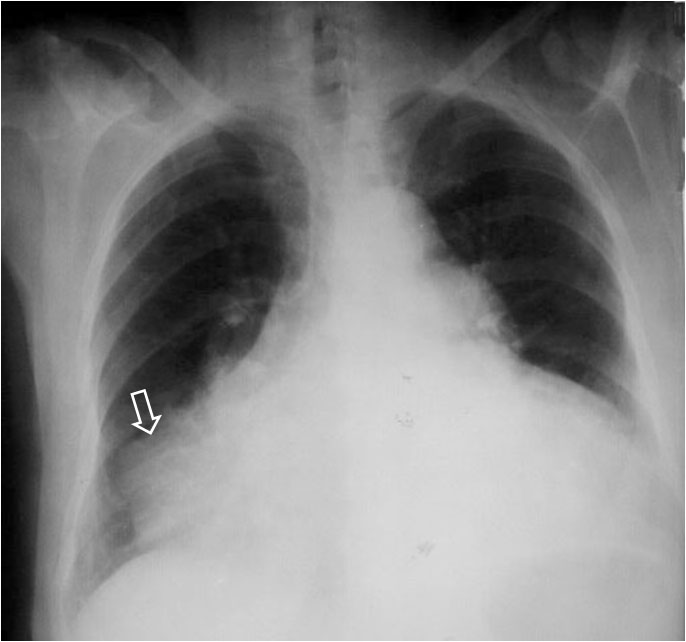

La irregularidad, abombamiento o borramiento del arco aórtico en la radiografía de tórax en bipedestación o en decúbito supino, en un paciente con traumatismo torácico, obliga a descartar rotura aórtica como causa de dicha alteración. La flecha muestra el contorno aórtico anómalo. Además, hay un aumento de densidad en el hemitórax izquierdo correspondiente a derrame pleural –hemotórax en este caso-, que refuerza la sospecha de rotura aórtica.